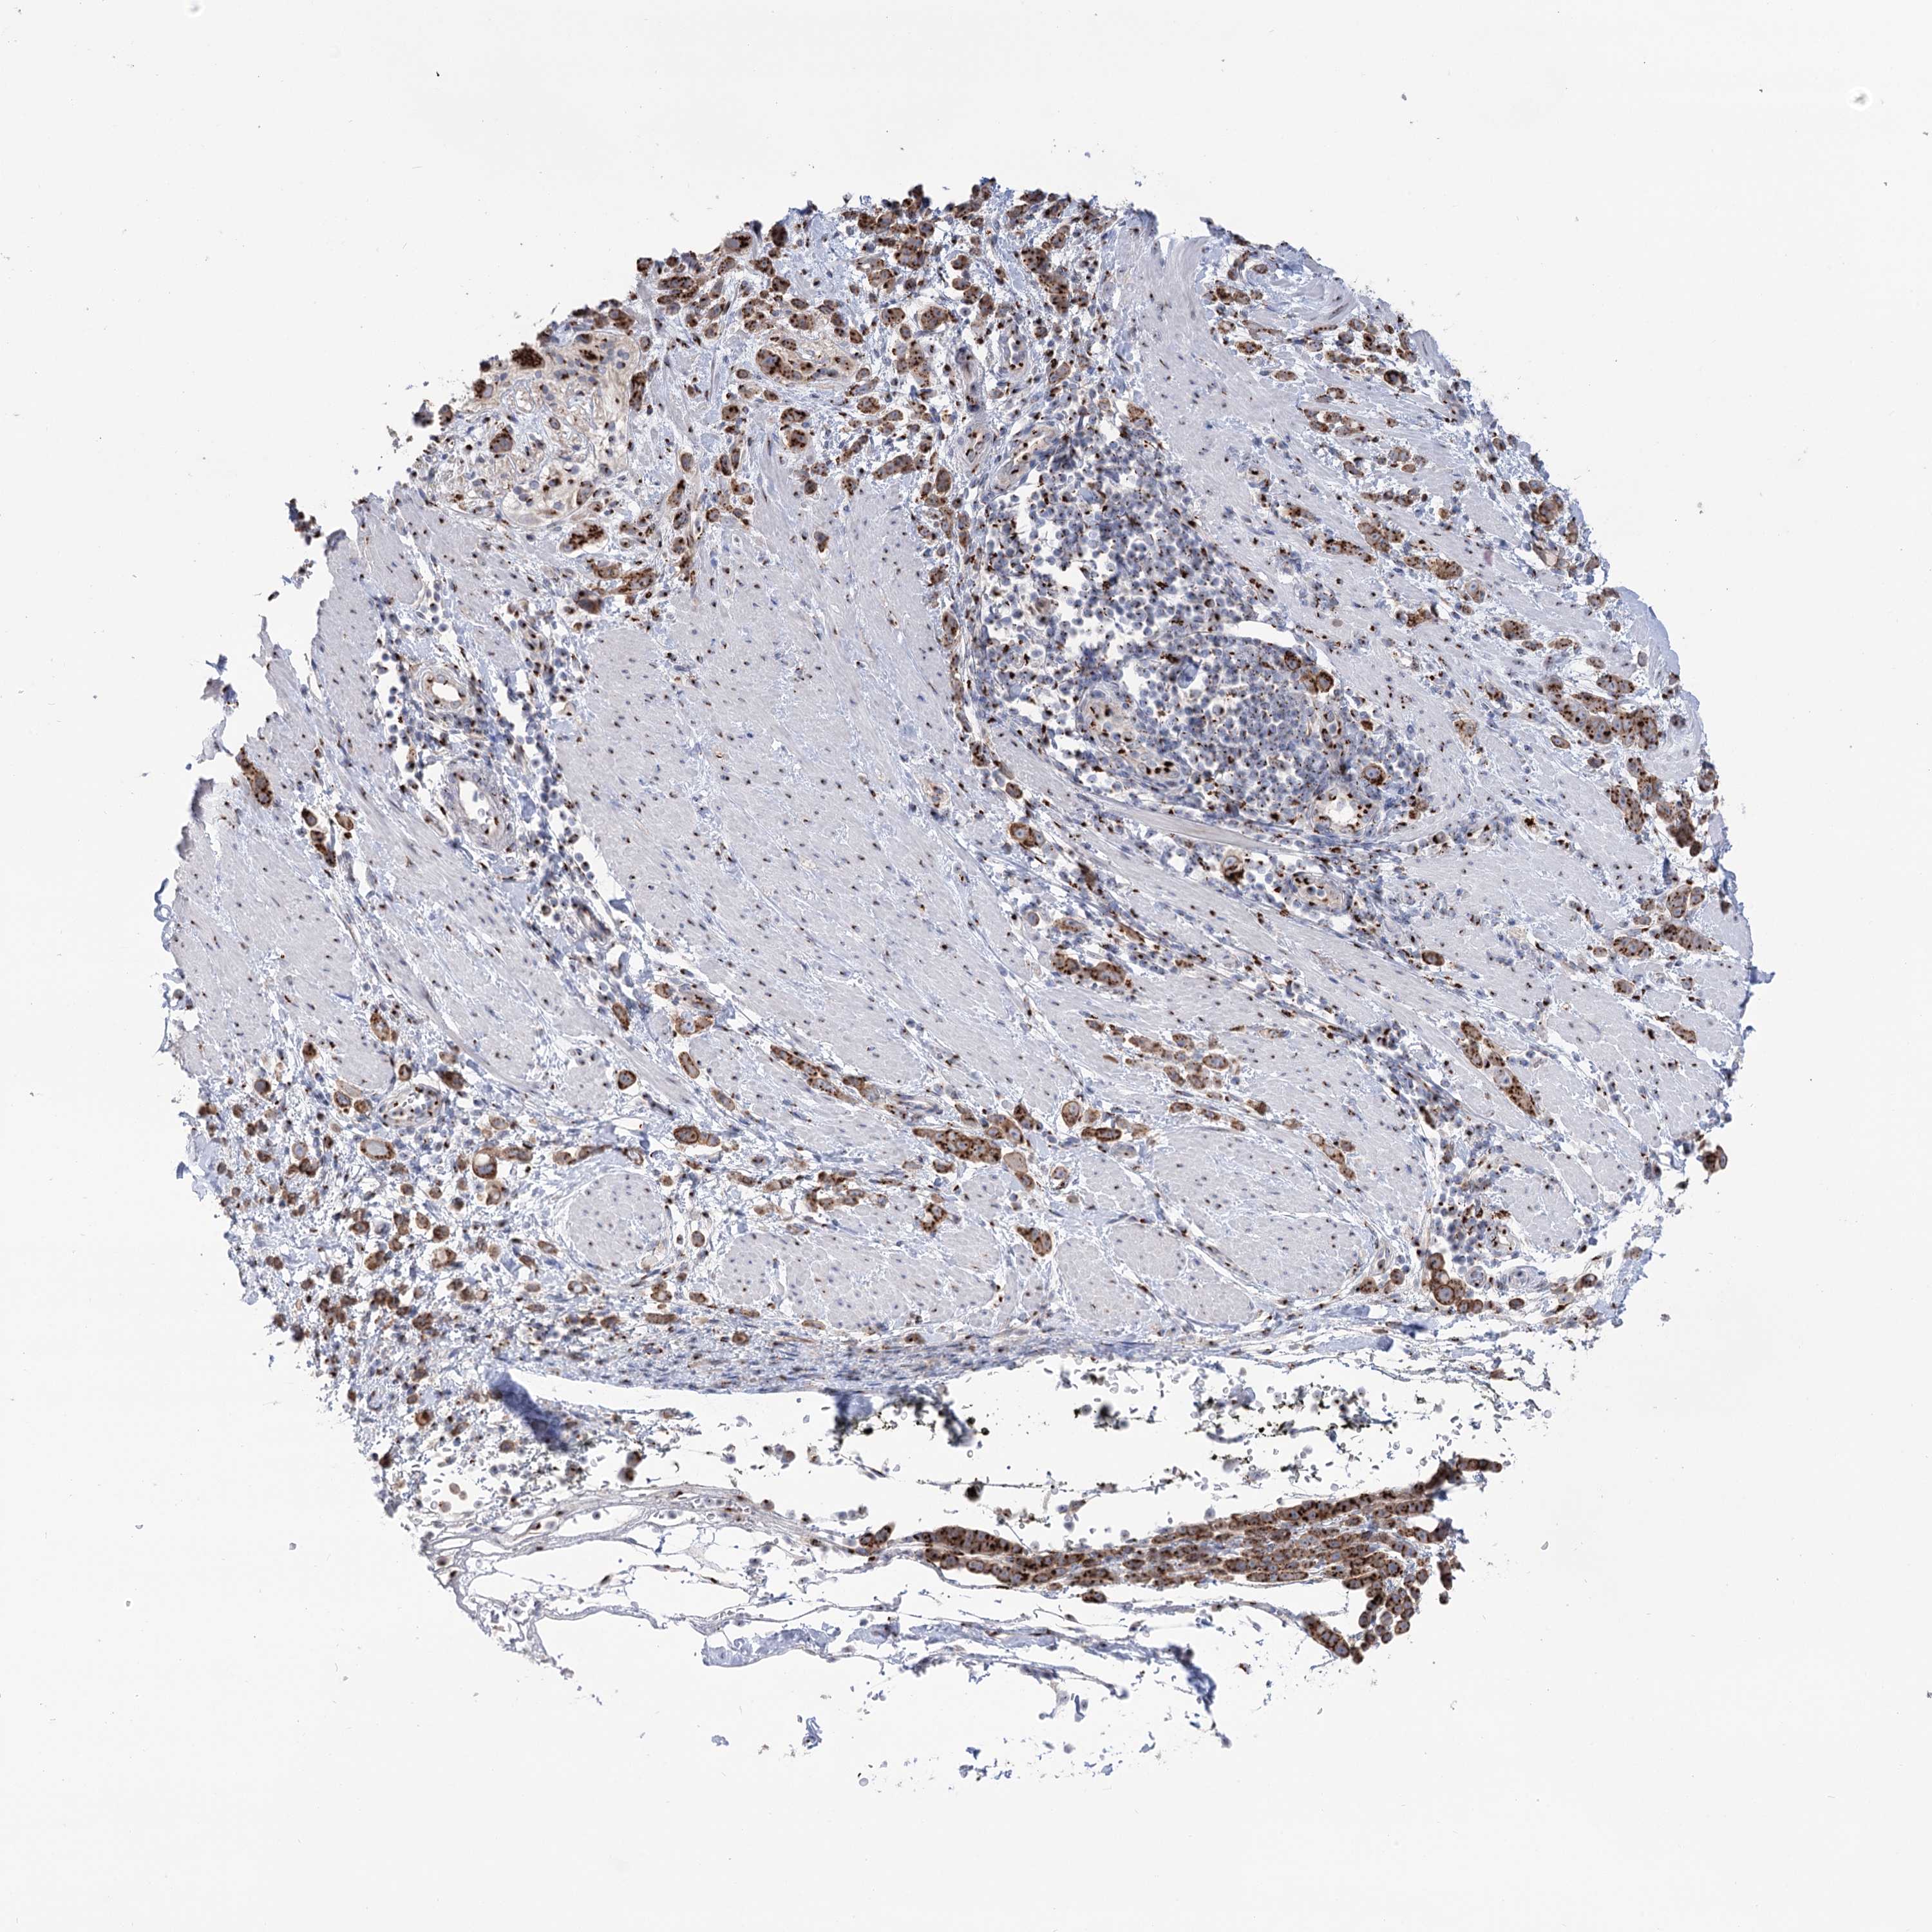

PANCREATIC CANCER - Protein expressioni

A mouse-over function shows sample information and annotation data. Click on an image to view it in a full screen mode. Samples can be filtered based on level of antibody staining by selecting one or several of the following categories: high, medium, low and not detected. The assay and annotation is described here.

Note that samples used for immunohistochemistry by the Human Protein Atlas do not correspond to samples in the TCGA dataset.

Antibody stainingi

Antibody staining in the annotated cell types in the current human tissue is reported as not detected, low, medium, or high, based on conventional immunohistochemistry profiling in selected tissues. This score is based on the combination of the staining intensity and fraction of stained cells.

Each image is clickable and will lead to virtual microscopy that enables deeper exploration of all samples and also displays staining intensity scores, fraction scores and subcellular localization as well as patient and tissue information for each sample.

Antibody HPA038299

Staining

High

Medium

Low

Not detected

Intensity

Strong

Moderate

Weak

Negative

Quantity

>75%

75%-25%

<25%

None

Location

Nuclear

Cytoplasmic/membranous

Cytoplasmic/membranous,nuclear

Adenocarcinoma, NOS